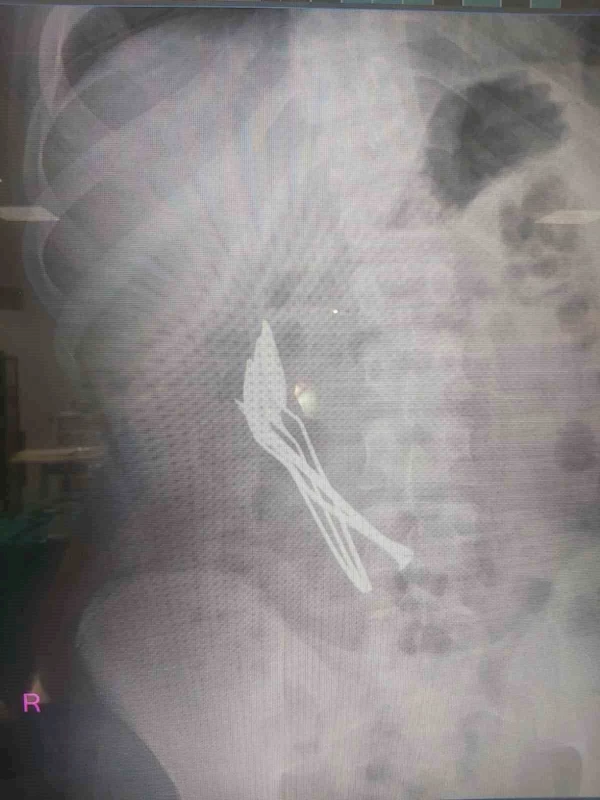

KAYSERİ'DE MİDE AĞRISI ŞİKAYETİYLE HASTANEYE BAŞVURAN ÇOCUĞUN MİDESİNDEN 4 METAL KAŞIK VE 1 ÇİVİ ÇIKARILDI.

Kentte yaşayan 15 yaşındaki çocuk, mide ağrısı şikayetiyle Kayseri Şehir Hastanesine başvurdu. Yapılan ilk müdahalede çocuğun röntgeni çekilirken, midesinde cisim fark edildi. Çocuk Cerrahisi ve Ürolojisi Anabilim Dalı Başkanı Doç. Dr. Mustafa Erman Dörterler tarafından ameliyata alınan çocuğun midesinden 4 adet metal çay kaşığı ve çivi çıkarıldı.